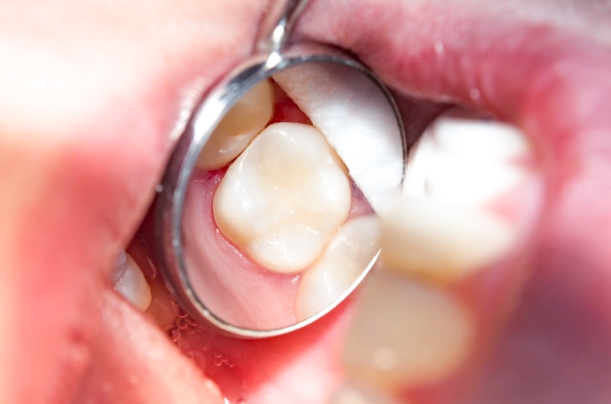

Root Canal Before and After in Mexico

Want to regain confidence in your smile? Our root canal gallery shows you real results: root canal pictures before and after that tell stories of transformation. Leave the pain and worry behind, and welcome a radiant, healthy smile. With our team of endodontic experts, each case is approached with care and precision, guaranteeing results that will take your breath away.

Do I Need a Crown After Root Canal?

Getting a dental crown after root canal therapy is an excellent way to preserve and protect a healthy tooth. However, not every tooth treated with endodontics needs a full crown. Depending on the damage to your tooth, our dentists will determine what kind of restoration is suitable.

For example, if an untreated cavity went deep into your tooth, a composite filling is better, but if your tooth suffered more damage on its cusps, insides, and sides, a tooth crown will be the right choice.